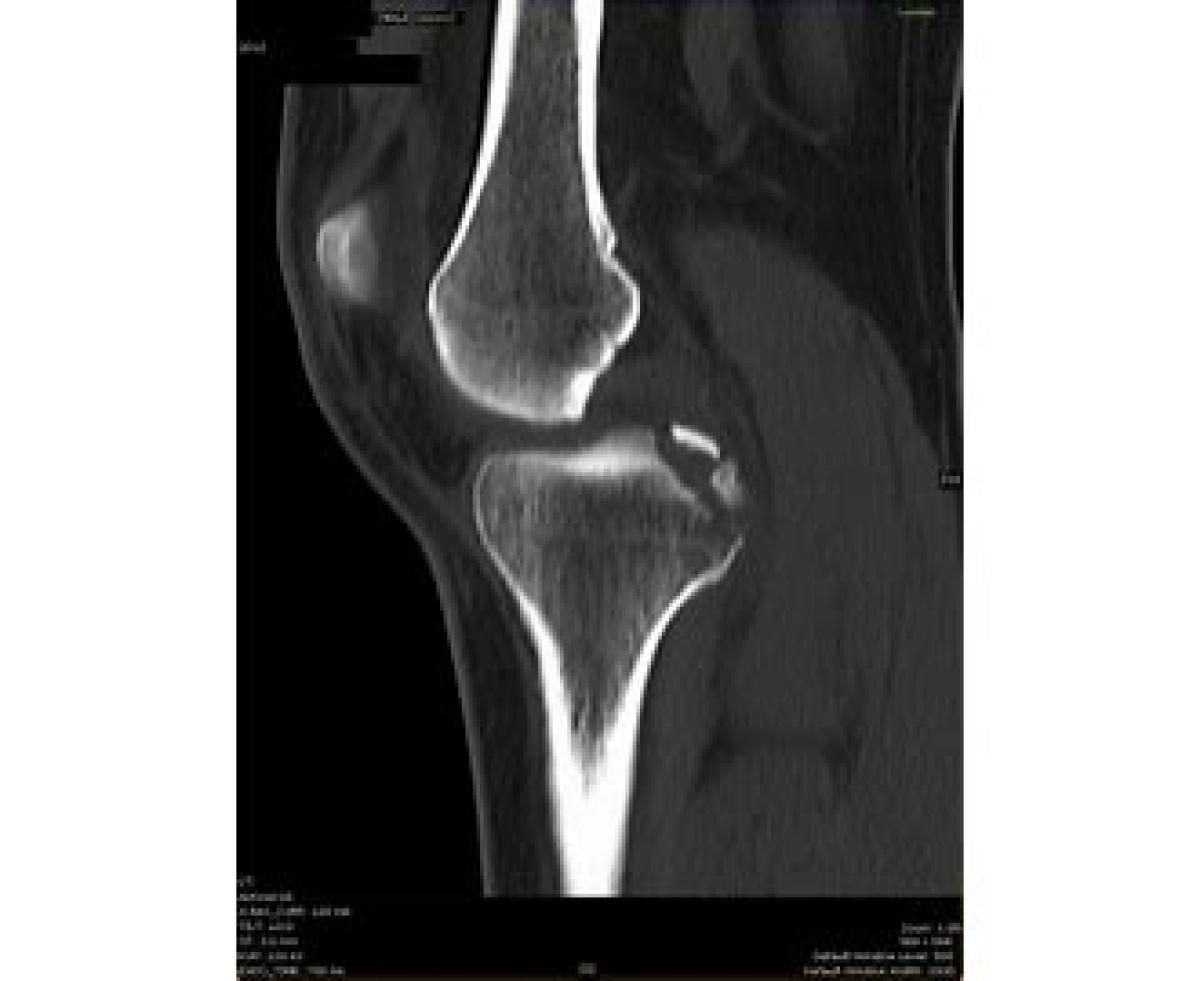

رباط متقاطع پشتی یا صلیبی خلفی یا PCL یکی از رباط‌های قوی مفصل زانو است. این رباط از کوندیل داخلی فمور (استخوان ران) به ناحیه پشتی بین کوندیلی تیبیا (درشت نی) متصل می‌گردد. رباط متقاطع پشتی (PCL) و متقاطع جلویی (ACL) داخل کپسولی بوده و به علت وضعیت آناتومیکی خاص به نام متقاطع یا صلیبی نامیده می‌شوند.

اگر کپسول مفصلی زانو از عقب باز گردد، اولین قسمتی که مشاهده می‌گردد، رباط متقاطع پشتی است. این رباط نسبت به رباط متقاطع جلویی، قوی تر بوده، ولی فیبرهای رباط متقاطع جلویی، وضعیت مایل تری دارند. مهمترین عمل رباط متقاطع پشتی، جلوگیری از دررفتگی تیبیا (درشت نی) به سمت عقب است.